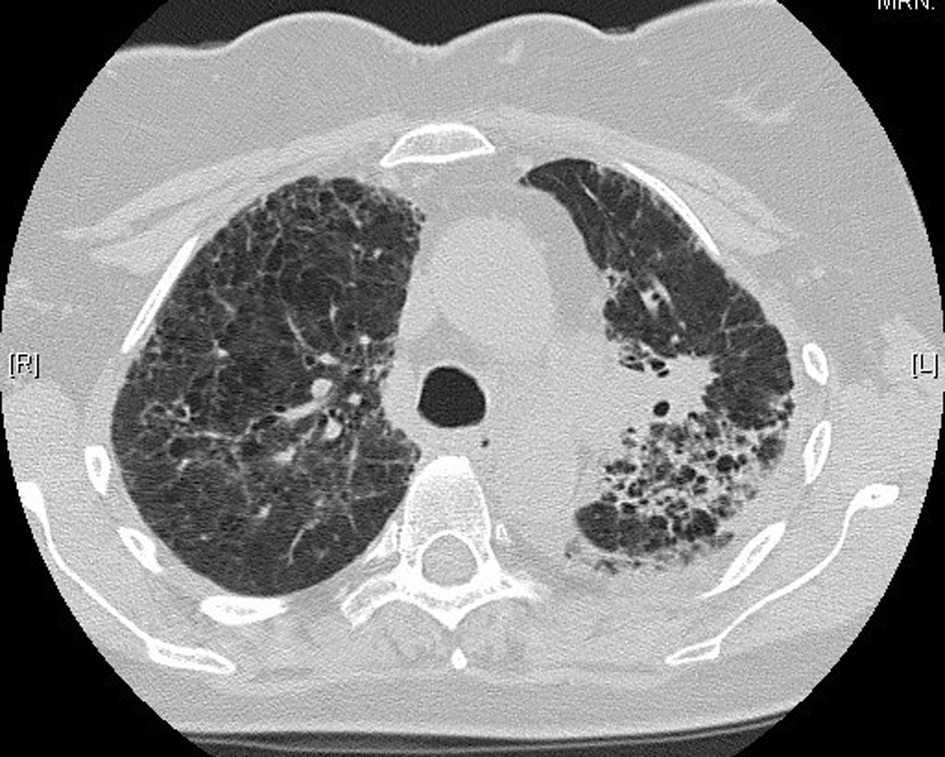

The patient returned home 10 days following hospital admission. She was not rechallenged with pemetrexed. High-resolution CT 1 month following her hospital admission showed interval resolution of the ground-glass attenuation, and complete resolution of the alveolar changes present during acute illness (Fig. 4). There was further resolution evident on repeat CT scanning 4 months post-illness (Fig. 5). She is currently on surveillance.

![]() Click for large image | Figure 5. Further resolution on computed tomography, 4 months post-illness. |